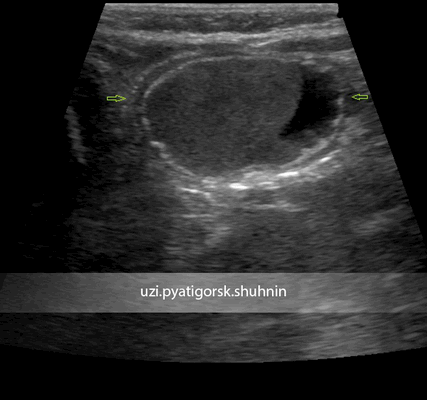

Однако есть важное отличие этих энтерогенных кист от кист яичника

- особое строение стенки энтерокистомы, содержащей элементы кишечной стенки: цилиндрический эпителий, Либеркюновы железы, ворсинки, гладкие мышечные волокна. Именно это отличие строения стенки кисты замечательно регистрируется с помощью методики УЗИ (см. фото).

Энтерокистомы часто остаются соединены с кишкой посредством тонкого соединительнотканного тяжа, их содержимое - негомогенное, иногда слоистое - слизь, холестерин, отторгнутый эпителий, что создает особенную УЗИ-картину.

УЗИ брюшной полости ребенка 3-х месяцев. Направлен с диагнозом «киста правого яичника». При исследовании выявлено кистозное образование, прилежащее к поверхности правого яичника, но не исходящее из него, со специфическим строением стенки, с негомогенным жидкостным содержимым. Диагноз кисты яичника исключен, установлен диагноз энтерокистомы. Пациентка направлена на консультацию хирурга. Своевременная и верная диагностика позволила уберечь ребенка от возможного негативного сценария развития этого заболевания.